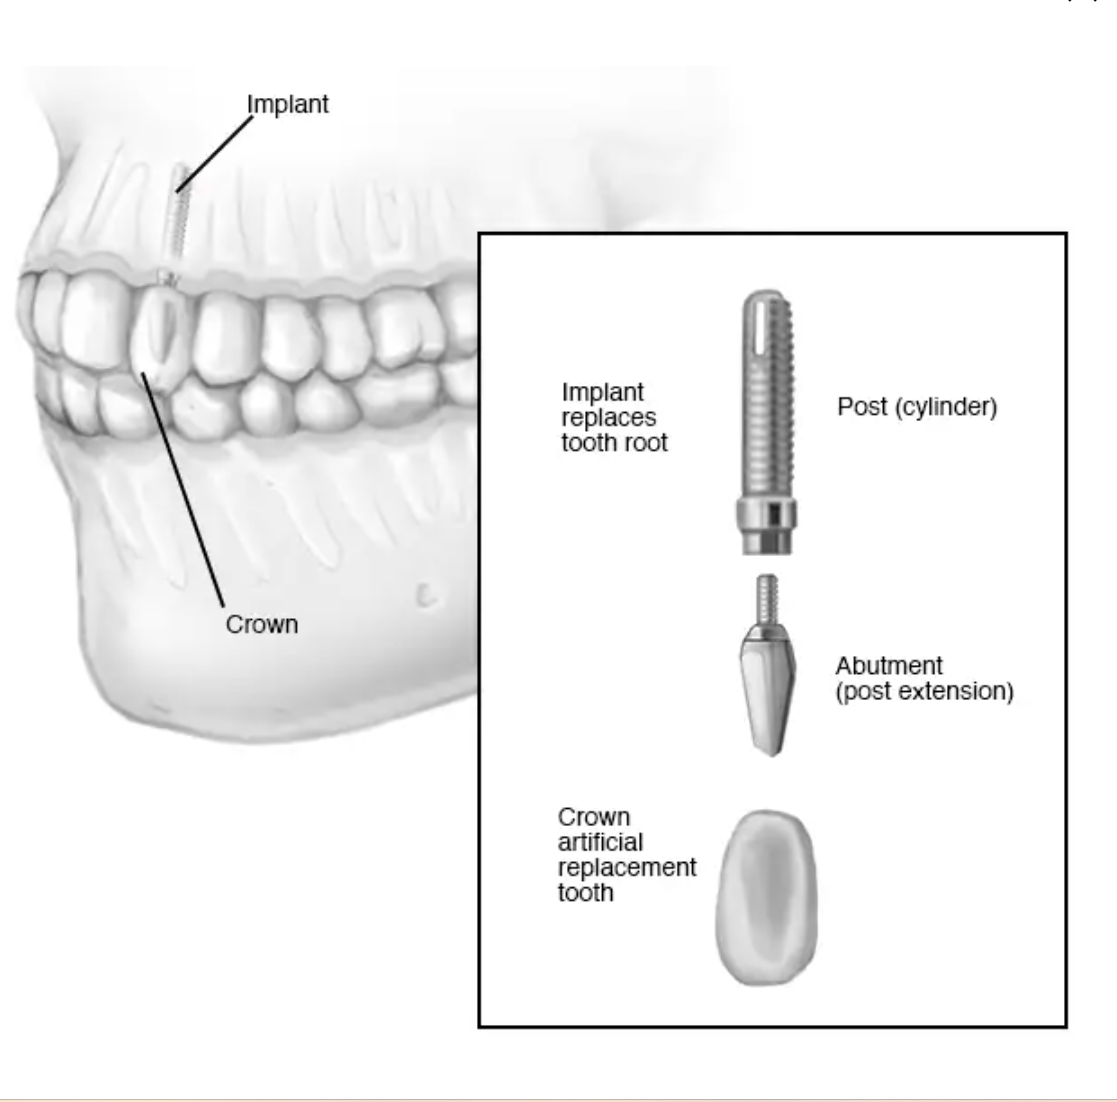

A dental implant is a specially designed titanium screw that is surgically implanted in a patient’s jaw as a tooth root replacement. The surgeon should get a 3d cone beam xray that shows the bone density of your jaw in 3 dimensions and insert the implant in place and direction so that it intersects the densest bone. Usually, several months are given after the dental implant surgery to allow the jaw bone to grow over and integrate (called “osseointegration”) with the implant, making it even stronger, before putting any biting force on the implant.

Because the best alignment of the screw for purchase in the densest bone may not be parallel with your other teeth, a custom titanium piece will be screwed onto the dental implant to properly orient the tooth. This is called a custom abutment. Then your general dentist will fabricate a zirconia crown that looks and functions like a tooth to tightly fit over the custom abutment.